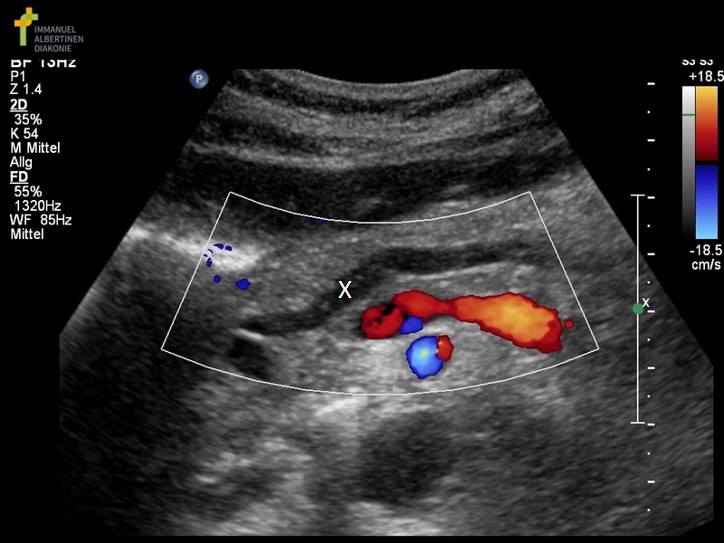

What structure is marked with the X on the image?

|

Which of the following structures is labeled #2?

gastroduodenal artery |

During an abdominal ultrasound, a small circular anechoic structure is identified at the anterior portion of the pancreas head. Color flow is identified in the structure. What is it?

celiac axis |